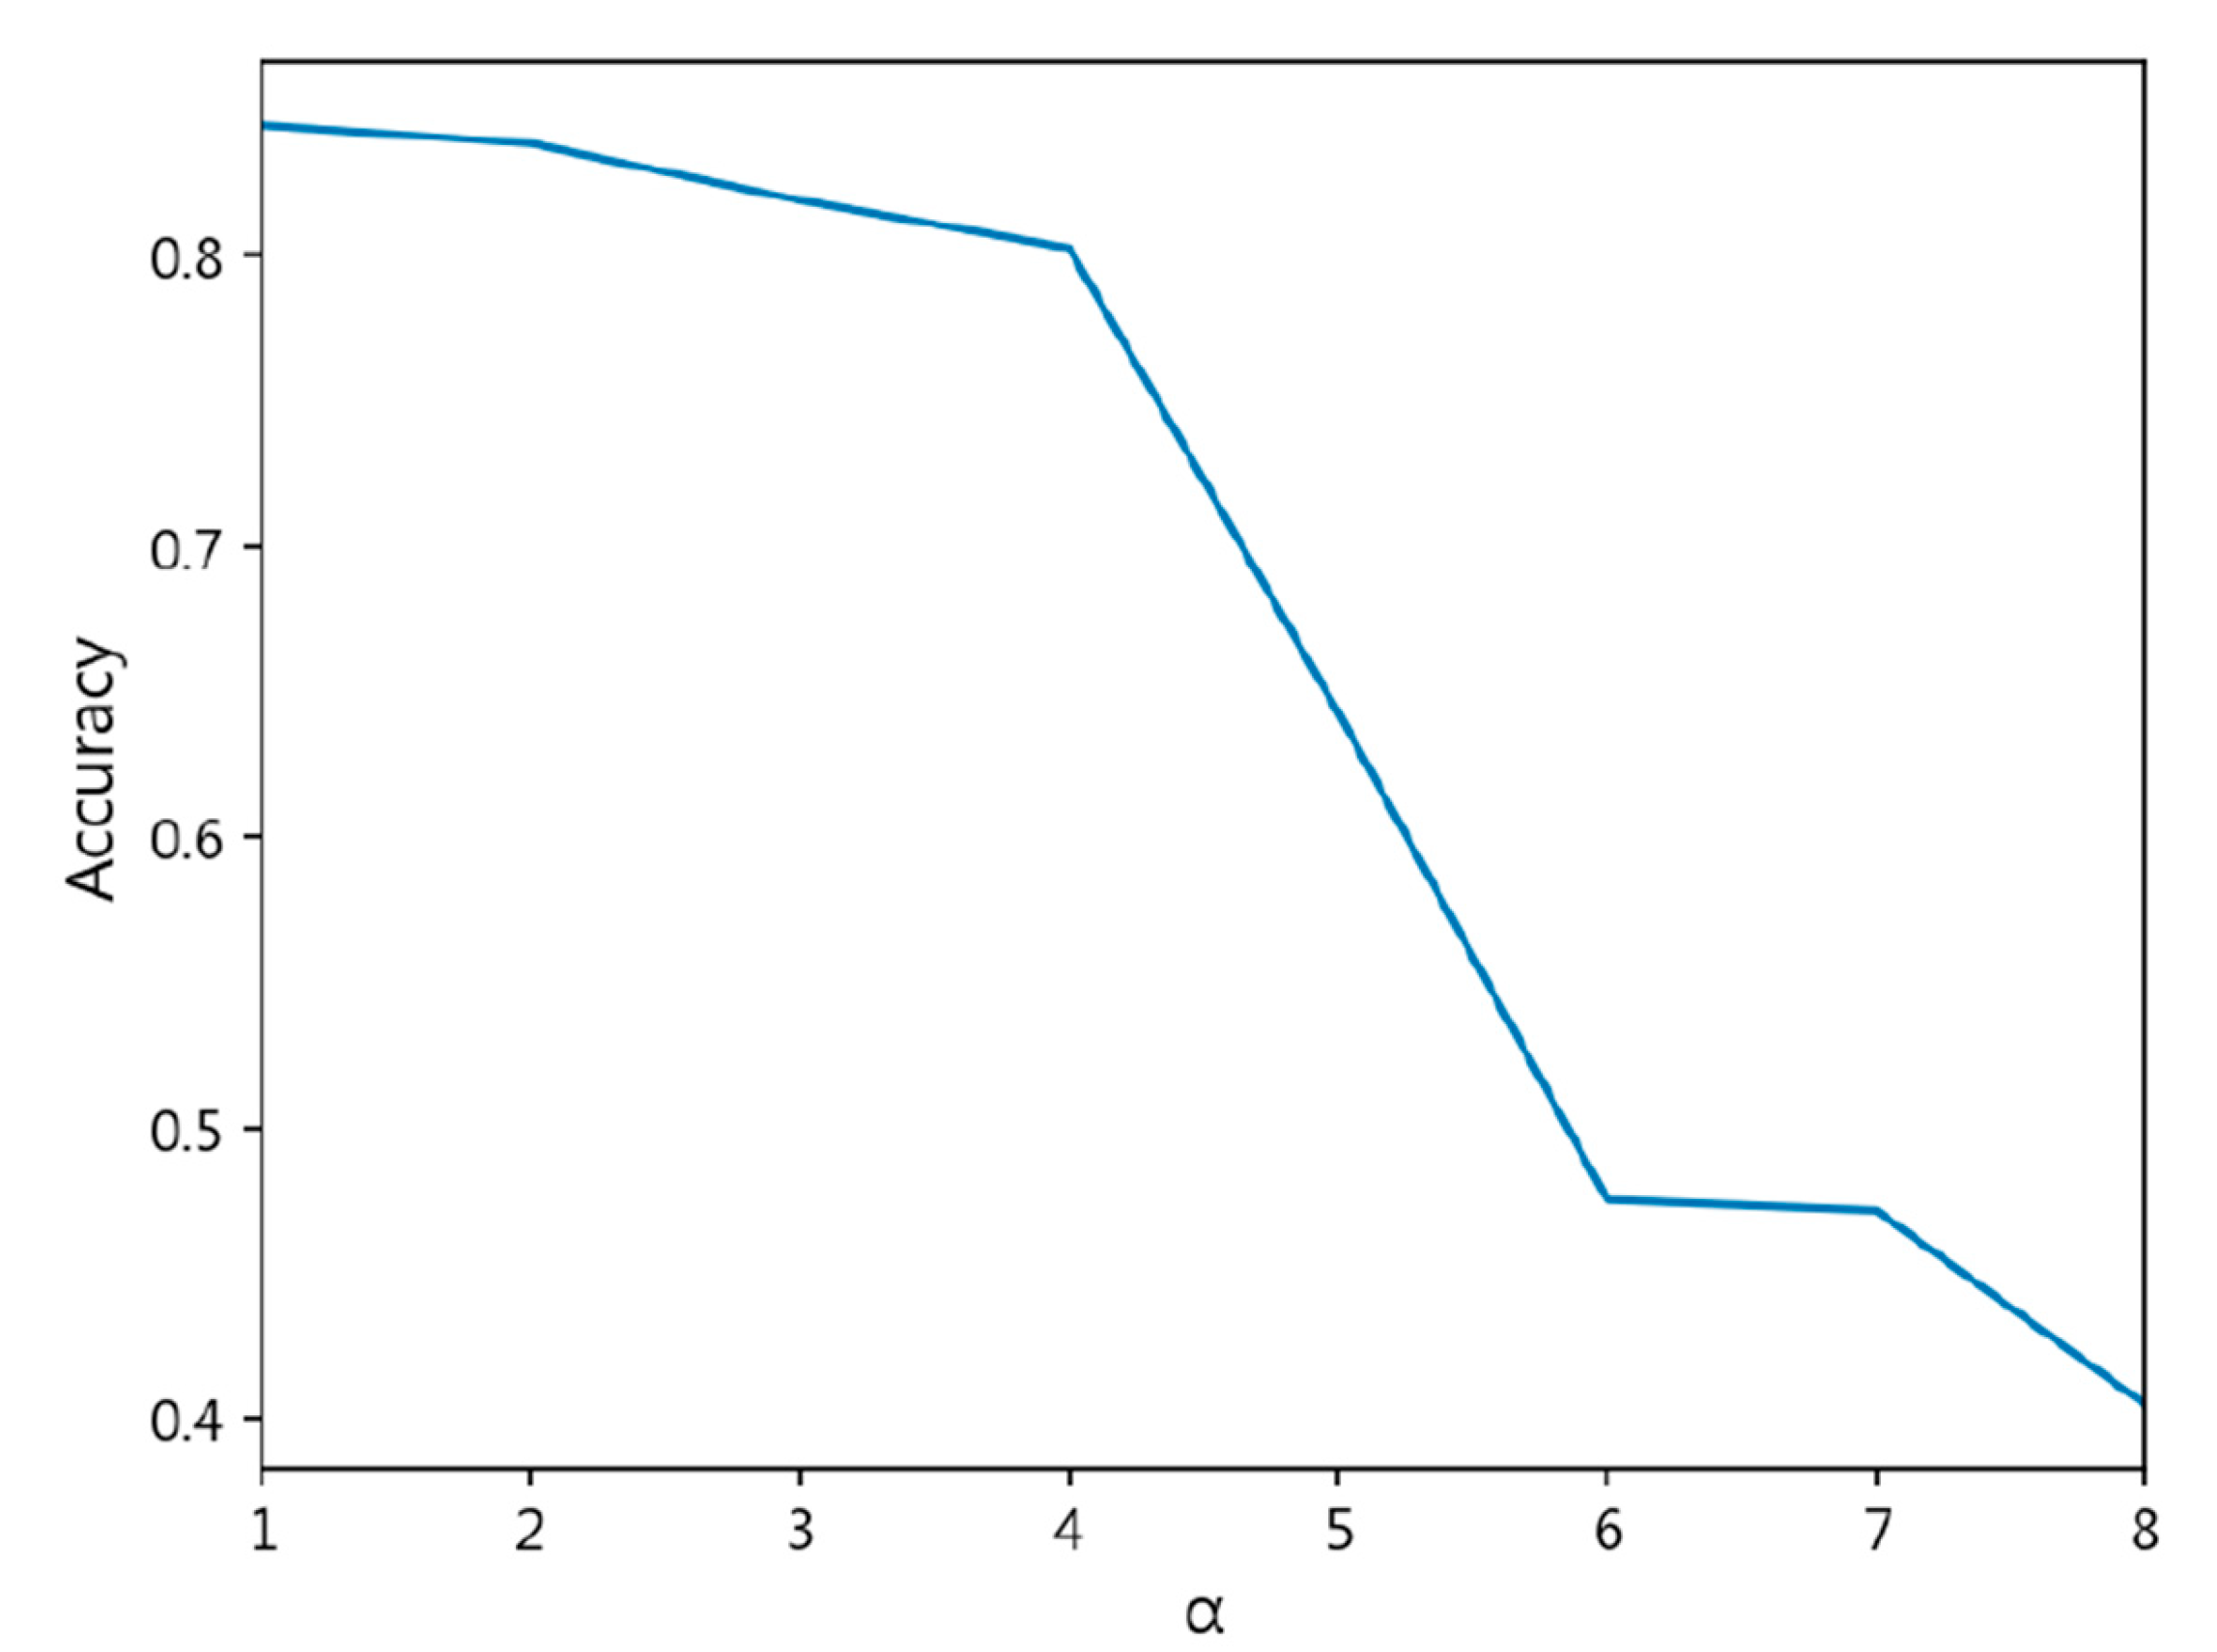

- The exponent a in the CDW-CE formula requires manual tuning of different values, making the process more time-consuming. Additionally, as a increases, the penalty intensity also increases, leading to higher loss values and longer training times.

- Through cross-validation training, larger a values result in less stable training, with a significant increase in standard deviation.

| CDW-CE | = 1 | 0.8447 ± 0.019 | 0.8441 ± 0.021 | 0.1652 ± 0.024 | 0.4309 ± 0.043 |

| = 2 | 0.8384 ± 0.018 | 0.8402 ± 0.017 | 0.1716 ± 0.016 | 0.4390 ± 0.018 | |

| = 3 | 0.8189 ± 0.028 | 0.8192 ± 0.027 | 0.1939 ± 0.026 | 0.4700 ± 0.029 | |

| = 4 | 0.8025 ± 0.037 | 0.8013 ± 0.037 | 0.2054 ± 0.036 | 0.4690 ± 0.037 | |

| = 5 | 0.6429 ± 0.095 | 0.5906 ± 0.142 | 0.3674 ± 0.096 | 0.6192 ± 0.080 | |

| = 6 | 0.4753 ± 0.039 | 0.3532 ± 0.029 | 0.5338 ± 0.038 | 0.7426 ± 0.026 | |

| = 7 | 0.4717 ± 0.030 | 0.3481 ± 0.022 | 0.5386 ± 0.032 | 0.7479 ± 0.026 | |

| = 8 | 0.4049 ± 0.115 | 0.2839 ± 0.112 | 0.8575 ± 0.614 | 1.1068 ± 0.700 | |

| = 9 | NaN | ||||

| = 10 | NaN | ||||